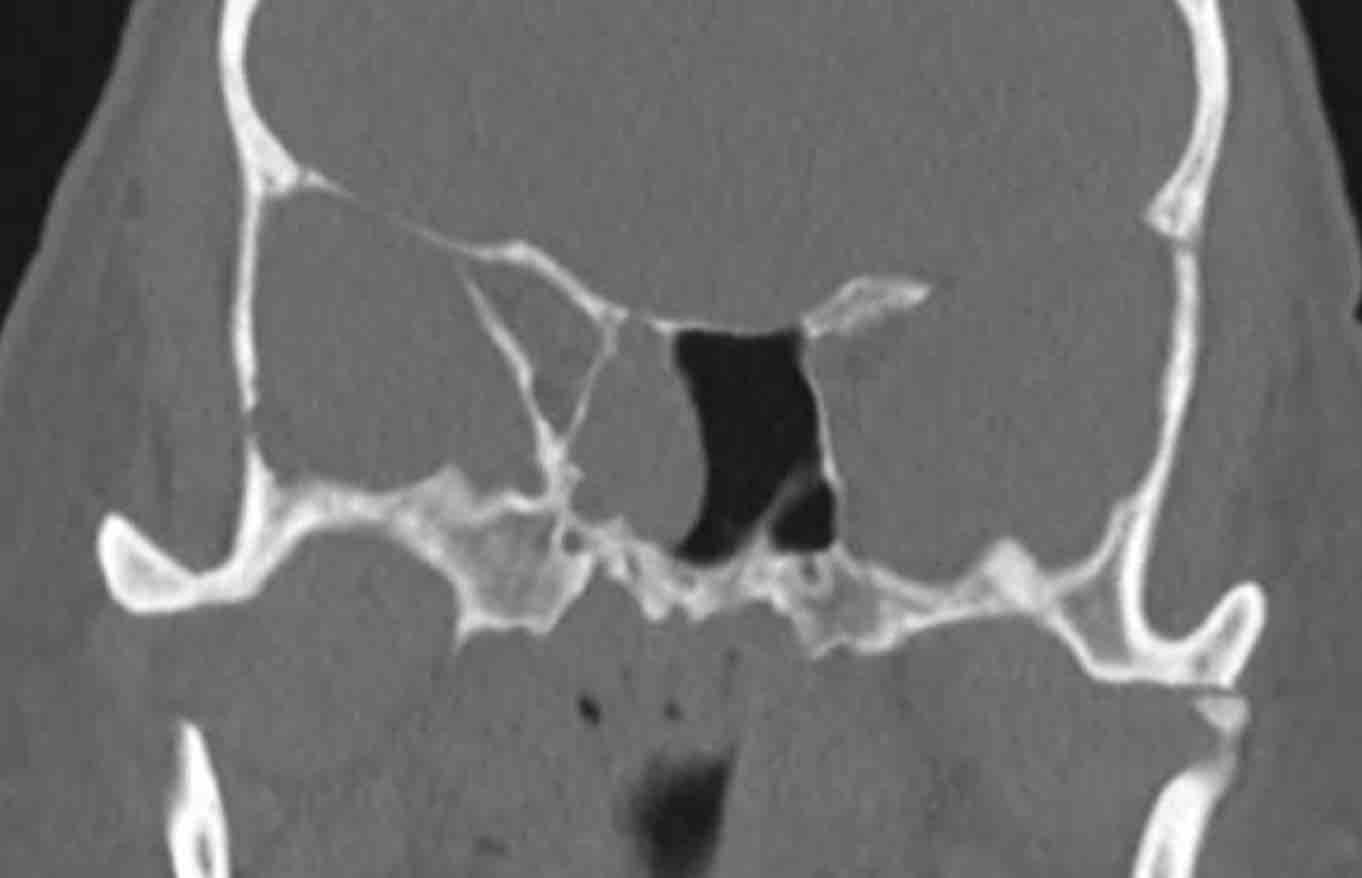

Có hình ảnh mờ đặc do mô mềm tại xoang hàm, xoang sàng và xoang trán bên phải (gọi là ‘kiểu tắc nghẽn phễu’).

Như đã đề cập, đây là một dấu hiệu cảnh báo.

Hãy quan sát các hình ảnh tiếp theo và cố gắng xác định liệu có tổn thương ác tính nào gây ra kiểu tắc nghẽn phễu này không (hay có nguyên nhân nào khác không?)